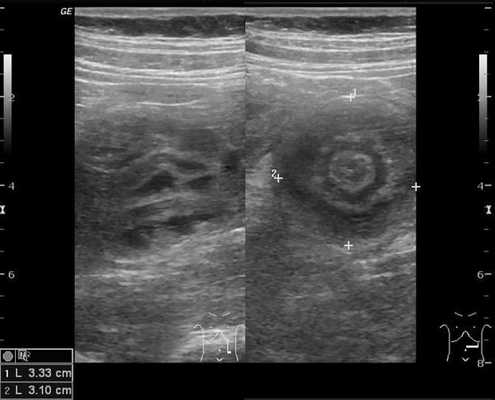

4. УЗИ брюшной полости позволяет выявить не только наличие жидкости, но и диаметр тонкого кишечника, толщину его стенки, маятникообразный характер перистальтики или отсутствие перистальтических движений.

Золотым стандартом считается проведение ультразвукового исследования (сонографии) органов брюшной полости, так как оно является неинвазивным, быстрым, безопасным, безболезненным и высоко информативным методом. [9] [10] При помощи сонографии можно диагностировать инвагинат не только на типичных, но и на атипичных участках кишечника, что повышает точность установления и верификации диагноза.

В момент УЗ-исследования врач может определить один из симптомов:

- симптом мишени (за счёт внедрения одной кишки в другую инвагинат на срезе выглядит как мишень);

- симптом "почки с завоздушенным центром".